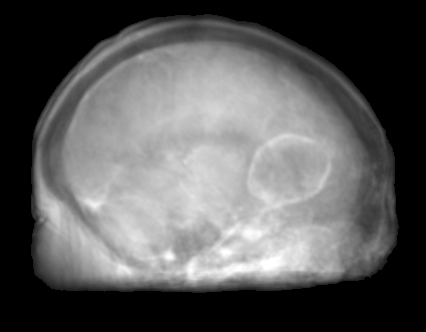

The proposed approach was successful in generating X-ray projections with a contrast similar to the one seen in true fluoroscopic X-ray images. Quantitative results of the generated projection images for all patients are presented in Tab. 2 and for the different network architectures in Tab. 2. In Fig. 2a to 2e the behavior of the MSE and SSIM w.r.t the projection angle is presented. Additional qualitative results of the proposed projection image-to-image translation pipeline for different patient data sets are shown in Fig. 3a to 3c. In Fig. 4 the influence of the modified network architecture, as well as the weighted loss w.r.t. to the edge map are presented.

MRI projection Generated projection Label projection

The improvement in our method compared to the baseline method is demonstrated by a decreased MSE, increased SSIM, and PSNR in Tab. 2. When examining Fig. 4a to 4c, improvements can be observed in the overall increased contrast of high-frequency details. Using the originally proposed architecture [5, 6], which gathers the residual blocks at the lowest resolution level, results in overall blurrier results and missing bone structures as seen in Fig. 4a. In contrast, the projections generated with the edge-weighted loss resemble the label images more closely. This can especially be observed at the base of the head. The projections created without the weighting also produce many high-frequency details in this region, however, these are less specific in comparison with the edge-weighted results. This results in decreased MSE and increased SSIM and PSNR of the projections synthesized using our approach. In addition, unnatural holes in the brain are generated by the baseline architecture. A possible explanation for the fluctuations in the error measure shown in Fig. 2a and 2b is that in our trajectory in the angles around 45 and 135 degrees the projection rays are cast from the side through the brain while around 90 and 180 degrees the angle of incidence is from the front or back side of the skull. In the first case this results in projections that exhibit large homogeneous areas which are easier to synthesize. In the second case, however, the high-frequency edges from the eyes, jawbone, etc. are the dominant structures in the image. A limiting factor of this study is the low number of patient datasets available. However, the amount of variation introduced by forward projecting the volumes is large. Varying projective geometries account for distinctively different structural appearance of the resulting projections. What is of course not covered by these transformations are unique characteristics of individual patients or different pathologies. To investigate the possible translation outcome of these properties larger datasets are required in the future. Also details that are not visible in the MRI projections can not be transferred to the generated images. An example would be interventional devices that are X-ray but not MR sensitive. Regarding subsequent post-processing applications, the question arises how this missing information in the generated projection images should be dealt with, which is subject to future work.